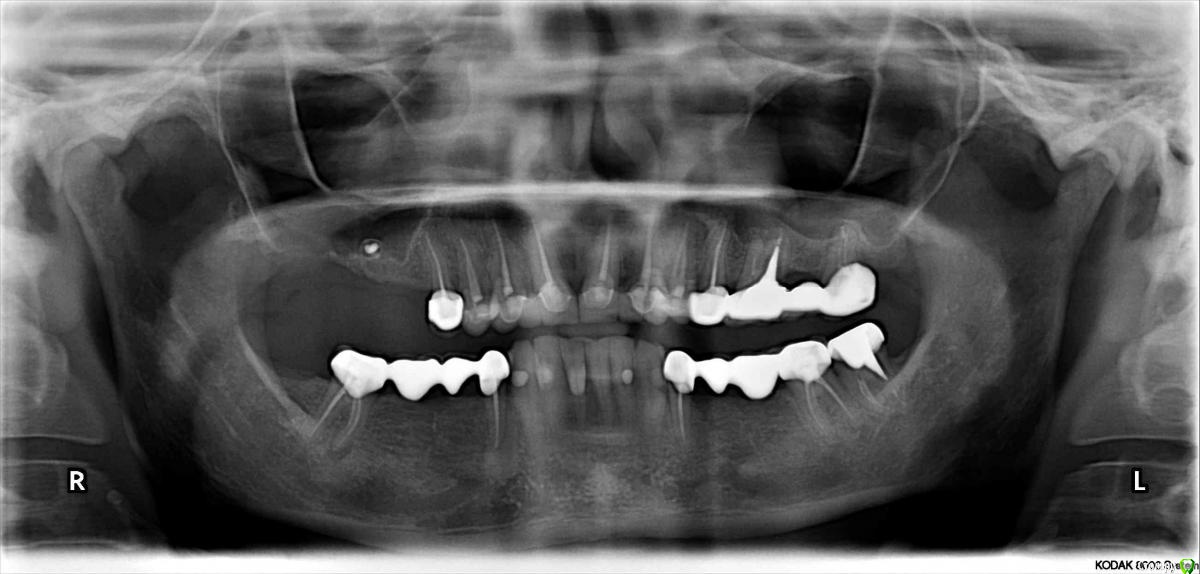

lazzal Опубликовано 29 октября, 2015 Поделиться Опубликовано 29 октября, 2015 Уважаемые хирурги-имплантологи, подскажите пожалуйста возможна ли в моем случае имплантация отсутствующих зубов верхней челюсти, какими имплантами (может мини?) и какая должна быть подготовка -может костная пластика? и возможна ли она? прилагаю 3 панорамных снимка - первый сделан в 2012 году сразу после протезирования всех зубов (делали одномоментно и верх и низ - половина зубов была абсолютно здорова, поднимали прикус таким образом, линия улыбки - безметалловая керамика), второй в апреле 2014г до удаления зуба на в.ч., третий в октябре 2015 (3 дня назад). От чего может быть такая убыль костной ткани? врач говорит, что теперь только бюгельный протез, может он с такими случаями не сталкивался? Возможно, опытные врачи на этом форуме увидят еще какие-то проблемы с зубами или деснами, на которые стоит обратить внимание. мне всего 32 года, я очень симпатичная внешне, очень хочется продлить жизнь своим зубам и не иметь проблем с жеванием. Заранее огромное спасибо всем откликнувшимся, буду Вам безмерно благодарна. Ссылка на комментарий

Bier Опубликовано 29 октября, 2015 Поделиться Опубликовано 29 октября, 2015 не вижу каких-то особых сложностей. Да потребуется нарастить кость, но случай вполне решаемый, особенно если пациентка "очень симпатичная внешне". С другими депульпированными зубами похоже тоже есть проблемы. Для более точной диагностики нужно КТ 2 Ссылка на комментарий

lazzal Опубликовано 29 октября, 2015 Автор Поделиться Опубликовано 29 октября, 2015 Bier, Вы в меня просто надежду вселили! Мой ортопед сказал, что у меня там все очень плохо, костной ткани нет совсем, да и по всей челюсти костная ткань очень бледного рисунка, т.е. слабая, хрупкая. сказал не ранее чем через 3 года при усиленном питании кальцием и желеобразующими и жирными продуктами и несколько курсов витаминов, возможно и можно будет подсадить, а так она не приживется. смысла в этом нет. ни один имплант по длине не подойдет, даже мини, тем более там гайморовая пазуха. еще сказал, какие тебе импланты, смотри, как бы все зубы не повыпадали, т.к. десны очень бледные. я в шоке была, конечно. так это можно начинать уже сейчас или все-таки кальций+ усиленное питание и укрепление десен? про кт - это надо именно этой области или обоих челюстей? Ссылка на комментарий

Bier Опубликовано 29 октября, 2015 Поделиться Опубликовано 29 октября, 2015 Bier, Вы в меня просто надежду вселили! Мой ортопед сказал, что у меня там все очень плохо, костной ткани нет совсем, да и по всей челюсти костная ткань очень бледного рисунка, т.е. слабая, хрупкая. сказал не ранее чем через 3 года при усиленном питании кальцием и желеобразующими и жирными продуктами и несколько курсов витаминов, возможно и можно будет подсадить, а так она не приживется. смысла в этом нет. ни один имплант по длине не подойдет, даже мини, тем более там гайморовая пазуха. еще сказал, какие тебе импланты, смотри, как бы все зубы не повыпадали, т.к. десны очень бледные. я в шоке была, конечно. так это можно начинать уже сейчас или все-таки кальций+ усиленное питание и укрепление десен? про кт - это надо именно этой области или обоих челюстей?Укрепление десен - это какая-то ерунда ну а кальций+здоровое питание не повредят конечно. Хотя кальций в таблетках я бы не рекомендовал, толку от него не много. К тому же думаю, что у Вас с ним все ок. Начинать можно уже сейчас. Возможно нужно провести проф. гигиену, возможно что-то полечить, ну и все, можно оперироваться. КТ нужно обеих челюстей. В каком вы городе? Ссылка на комментарий

DmitrySH Опубликовано 29 октября, 2015 Поделиться Опубликовано 29 октября, 2015 Не хочу огорчать, но кроме хирургии и ортопедии еще немного эндодонтии потребуется. Ссылка на комментарий

DmitrySH Опубликовано 29 октября, 2015 Поделиться Опубликовано 29 октября, 2015 А что такое ЭНДОДОНТИЯ? В вашем случае: повторная ревизия каналов у зубов 26, 47. (28, 38 - вопрос в целесообразности сохранения) Возможно какие-то зубы во фронте, по ОПТГ непонятно Ссылка на комментарий